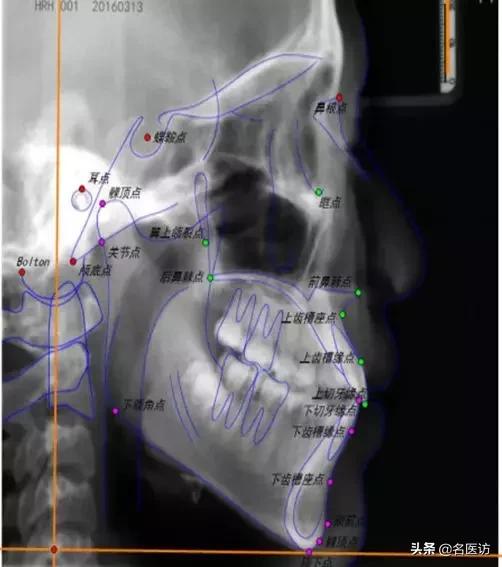

医生会用很多标志点和平面来分析侧位片,天使君很难将所有的点一次跟天使er们介绍清楚。这次来跟天使君一起了解下几个常用的侧貌美学分析依据。

1、评估面型:SNA角

面型可粗略的分为3大类:直面型、凸面型、凹面型。其中,直面型是公认的最符合审美的面型,SNA角可以帮助我们了解自己的面型和凹凸度。

N:鼻根点,鼻额缝的最前点

S:蝶鞍点,蝶鞍影响的中心

A:上牙槽座点,鼻子和上牙槽接触的最凹点